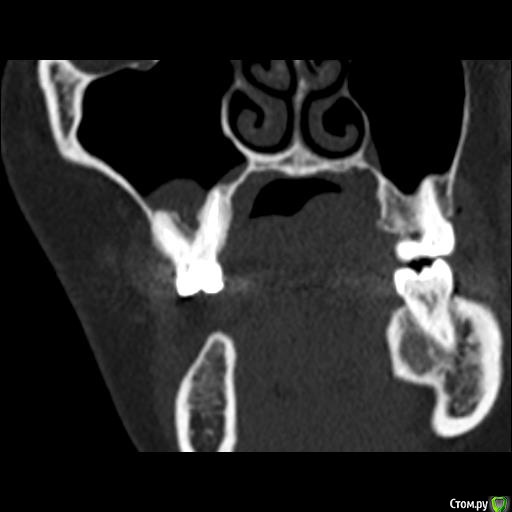

Юлия2386 Опубликовано 30 июля, 2020 Поделиться Опубликовано 30 июля, 2020 Добрый день, уважаемые врачи! Прошу вашей помощи, так как уже замучалась я конкретно. У меня уже 9 месяцев боли в правой стороне лица давящего характера. Давит на лоб, глаз, иногда висок. С декабря 2019 выявили фронтит-гайморит, проходила лечение у Лора и ещё невролога. Окончательного результата по выздоровлению за это время не достигнуто. Видимо это одномерный гайморит, так как постоянно какое-то воспаление формировалось у зубов 1.6;1.7;1.8. Многие стоматологи не видят проблем в зубе 1.6. Посоветовали удалить зуб 1.8 так как там был глубокий десневого карман. Удалила, а воспаление разрослось ещё больше (после удаления поцарапала щеку зубом 1.7, возможно из-за этого разрослось воспаление?!) После удаления прошёл месяц, а картина сейчас такая https://yadi.sk/d/ziceEN_jVZ9IkwВ итоге последний врач сказал, что все-таки проблема идёт от зуба 1.6, так как не запломбирован один канал, но из-за того что у зуба входят корни в гайморовых пазуху, лечить его не видет смысла, порекомендовал его удалить и через лунку вычиститься всю слизь, но он этим не занимается. Теперь я замешательстве и не знаю, что мне с этим делать, а самое ужасное, что глаз от этого болит( Уважаемые доктора, очень прошу вашей помощи, выскажите пожалуйста ваше мнение и может посоветуете к кому с этим можно обратиться в Москве. Ссылка на комментарий

wladdX Опубликовано 31 июля, 2020 Поделиться Опубликовано 31 июля, 2020 Представленная спиральная КТ не позволяет детально рассмотреть корневые каналы зубов и тп, чтобы получить какое-то внятное суждение.На уровне зубов 18, 17 и 16 есть локальное утолщение слизистой оболочки синуса и это всё, что из этого исследования можно выяснить. Адекватность обтурации корневых каналов зуба 16 оценить не представляется возможным (по крайней мере в моём понимании).Я бы порекомендовал сделать КЛКТ (конусно-лучевую компьютерную томографию), используемую в стоматологии. Ссылка на комментарий